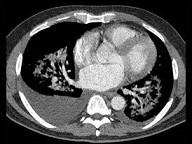

问题 男,51岁,呼吸困难,心悸,咳大量粉红色泡沫痰,结合CT,最可能的诊断是 ( )

选项 A.肺泡性肺水肿 B.间质性肺水肿 C.肺泡癌 D.肺泡蛋白沉积症 E.肺结核

答案 A